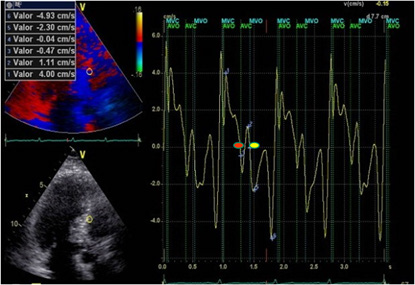

Figure 2: LVPPMC curve in a patient with HFpEF. The red dot indicates the beginning of the phase and the yellow dot its completion. Duration 160ms; left ventricular mass: 106gr/m2; relative wall thickness: 0.49%.

A significant increase of LVPPMC time was found in Group III patients with HFpEF compared with the group without heart disease (Group I and II). Moreover, in these cases the tissue strain curve loses its sharp slope and becomes irregular needing a more prolonged time to generate the necessary pressure difference to open the mitral valve (Figure 1 and 2). This variable correlates with the E/E’ ratio, since in Group I this was 6,34±1,46 compared with Group II that reached a value of 7,50±1,53 and the Group III which reached a value of 16.13±6.47 (p<0.01) (Table 1). An abnormal effect can be interpreted in the negative pressure generated in this phase, evidencing a delayed process with longer time to open the mitral valve [7] (Figure 1 and 2). We also observed that the diastolic duration (passive filling phase without energy consumption) was maintained with scant variation in all groups (354ms in the Group I; 471ms in the Group II and 333ms in the Group III), confirming that the altered suction mechanism occurring in the LVPPMC mainly participates of the dysfunctional process. The increase in LVM, RWT and VAI in Group III, all with significance, are measurements that correspond to an increase in PAP to 32mmHg in Group III in relation to Groups I and II of 22mmHg. These concepts would explain why in HFpFE a pulmonary wedge pressure ≥15 mmHg or a left ventricular end-diastolic pressure ≥16 mmHg is usually found [8]. The possible interpretation is that as the LV mass increases it does not reach suitable detorsion in a normal time to generate a drop in pressure with adequate slope to open the mitral valve.